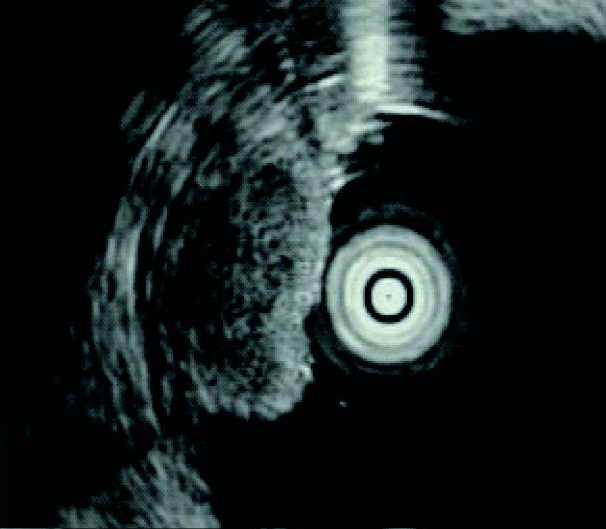

An endoscopic ultrasound of a neuroendocrine tumor (NET) in the upper gastrointestinal tract (duodenum).

Credit: BMC Gastroenterol 2011. doi: 10.1186/1471-230X-11-67 CC 2.0.